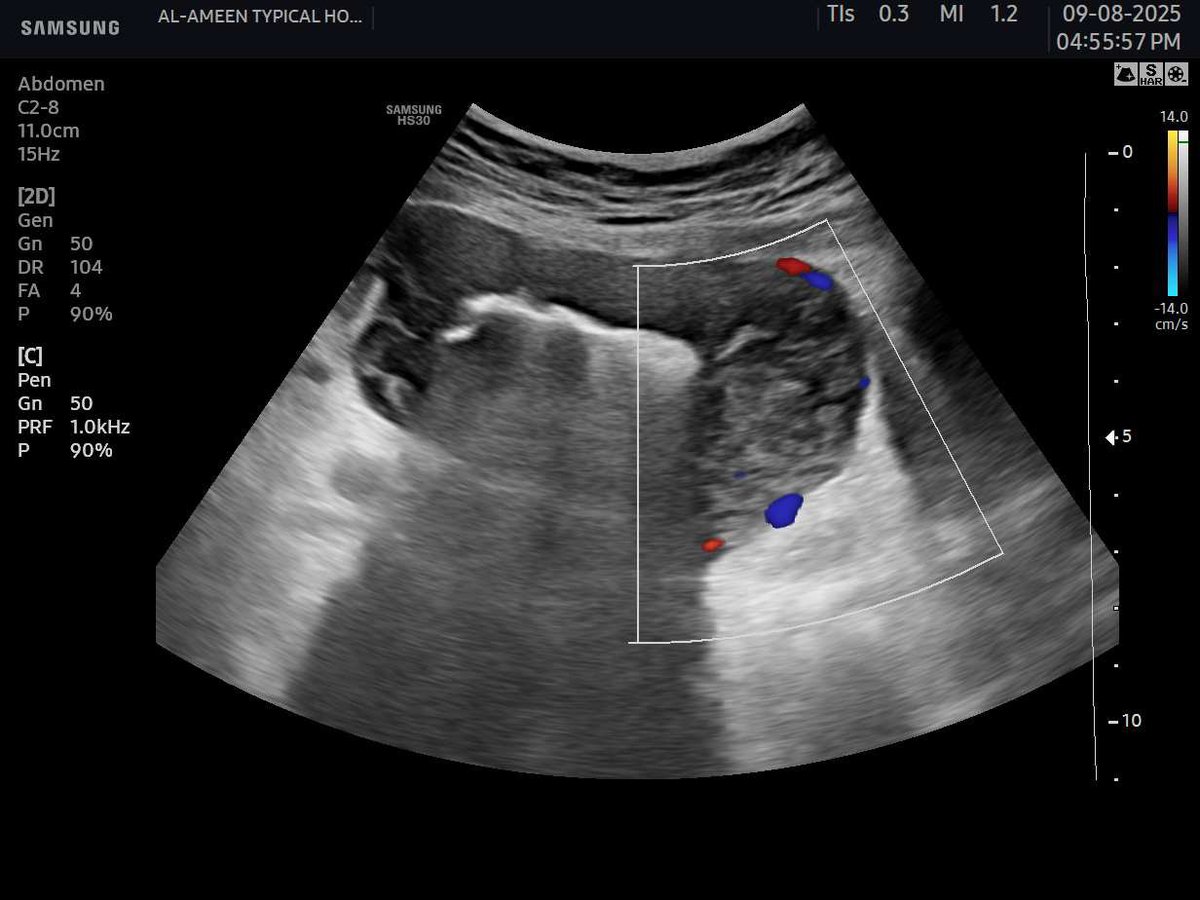

45 years female Presented with diffuse abdominal pain , persistent vomiting and bloody stool And a palpable abdominal mass seen to the RT of the umbilicus #EchoTech #Ultrasound #GIT

45 years female Presented with diffuse abdominal pain , persistent vomiting and bloody stool And a palpable abdominal mass seen to the RT of the umbilicus #EchoTech #Ultrasound #GIT

45 years female Presented with diffuse abdominal pain , persistent vomiting and bloody stool And a palpable abdominal mass seen to the RT of the umbilicus #EchoTech #Ultrasound #GIT